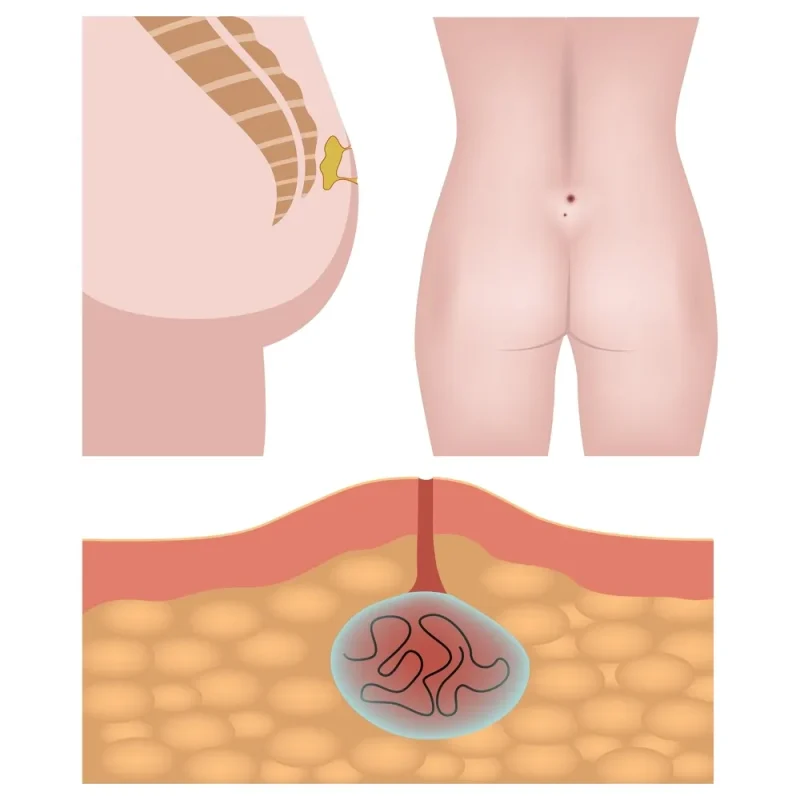

۴. کیست مویی یا سینوس پیلونیدال

کیست مویی اغلب در ناحیه بالای مقعد و میان دو سر باسن ایجاد میشود و معمولاً در اثر تجمع مو در زیر پوست به همراه التهاب و عفونت بروز مییابد. علائم آن شامل تورم، درد، قرمزی و در برخی موارد ترشح چرک و خون است.

بررسی و درمانهای قطعی کیست مویی یا سینوس پیلونیدال

کیست مویی یا سینوس پیلونیدال (Pilonidal Sinus) یکی از بیماریهای نسبتاً شایع ناحیه پایین کمر و ناحیه ساکروکوکسیژیال (بین دو باسن) است که اغلب در میان جوانان، بهویژه مردان پرمو، افراد کمتحرک یا دارای شغل نشسته دیده میشود. این بیماری ماهیتی التهابی و عفونی دارد و زمانی رخ میدهد که تعدادی از موها بهصورت معکوس وارد پوست شده و بهمرور موجب ایجاد التهاب، حفرههای چرکی و مجاری زیرپوستی میشوند.

در این شرایط، موهای ریخته شده در ناحیه پایین کمر، بهواسطه فشار و اصطکاک وارد فولیکولهای پوست شده و بهعنوان جسم خارجی، باعث ایجاد واکنش التهابی مزمن میشوند. بهتدریج، بدن برای محصور کردن این موها و ترشحات، یک کیست یا سینوس ایجاد میکند که اغلب به آبسه و عفونت ختم میشود.